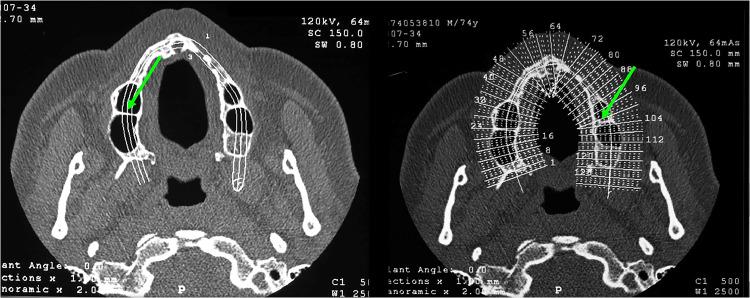

MATERIALS AND METHODS

A retrospective cohort study conducted at a single medical centre. Individuals who underwent maxillary sinus floor augmentation for dental implant placement via the lateral approach. Preoperative imaging was evaluated for anatomical variables, including the presence of septa, alveolar antral artery, Schneiderian membrane thickness, maxillary sinus lateral wall thickness, residual alveolar bone height, and maxillary sinus shape. Univariate and multivariable analyses assessed the associations between anatomical factors and EIF. A P value <.05 was considered significant.

材料与方法

在单一医疗中心进行一项回顾性队列研究。纳入通过外侧入路进行上颌窦底提升以植入牙种植体的个体。对术前影像进行解剖学变量评估,包括间隔的存在、牙槽窦动脉、施奈德膜厚度、上颌窦外侧壁厚度、剩余牙槽骨高度以及上颌窦形状。单因素和多因素分析评估解剖学因素与EIF之间的关联。P值<0.05被认为具有统计学意义。